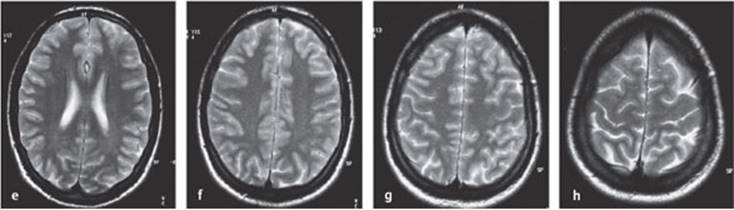

Fig. 4.6 a–h Normal MRI of the brain in 5 mm sections from the base of the brain to the vertex.